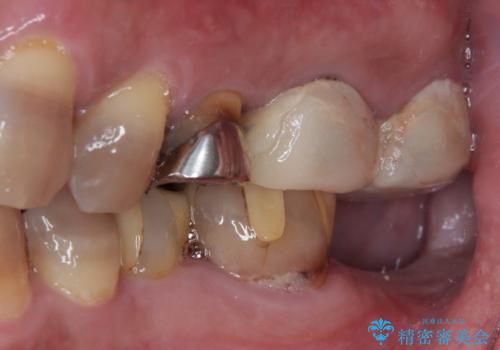

左下はインプラントによる補綴治療を行いました。

- 外科手術のため、術後に痛みや腫れ、違和感を伴います

- メンテナンスを怠ったり喫煙により、お口の中に大きな悪影響を及ぼすインプラント周囲炎等にかかる可能性があります